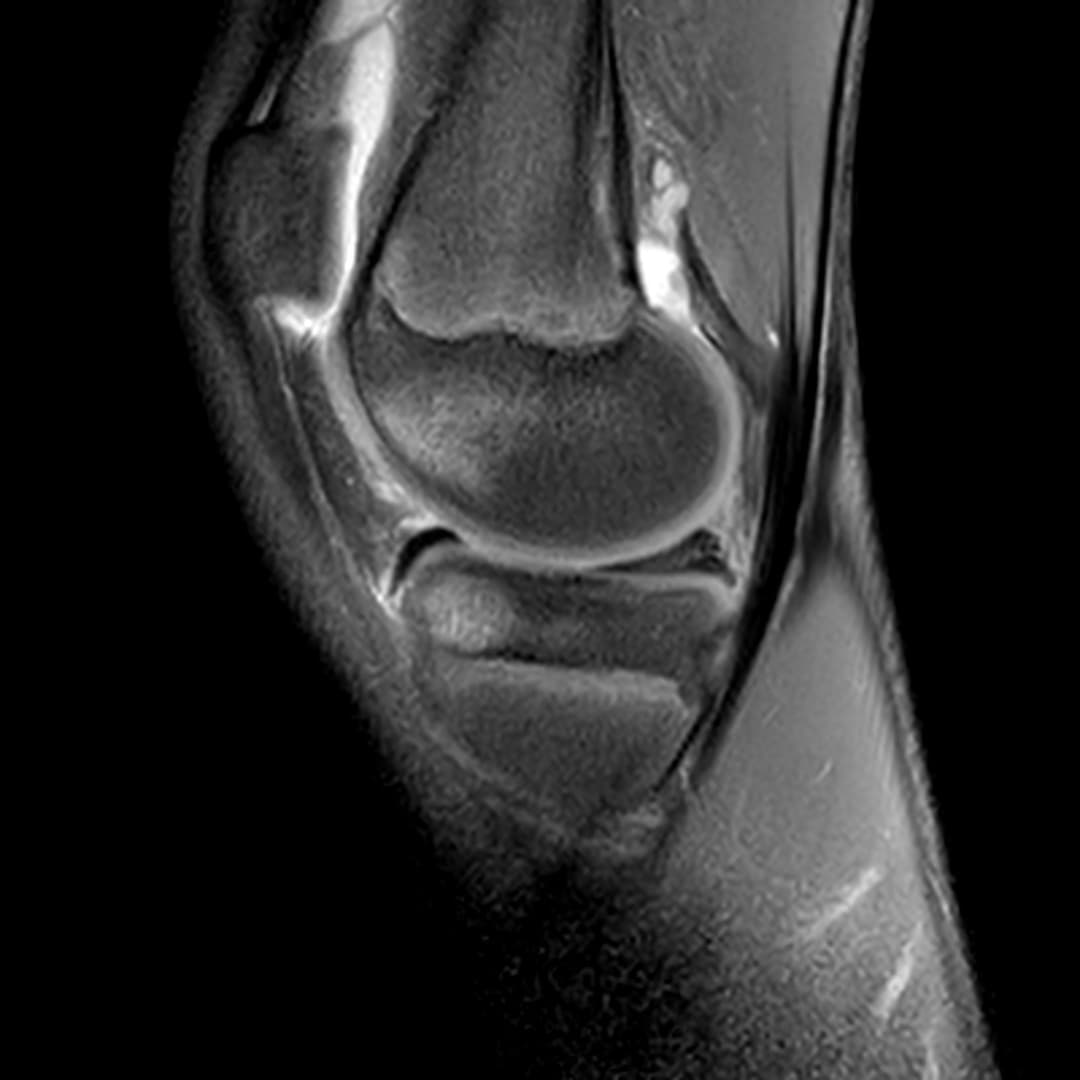

Contusion osteo-chondrale du genou

Présentation clinique

Douleurs post traumatique et gonflements

IRM

Intégrité ligamentaire et méniscale

Fracture sous chondrale par impaction avec œdème sous chondral en miroir du compartiment fémoro-tibial médial.

Epanchement articulaire abondant.